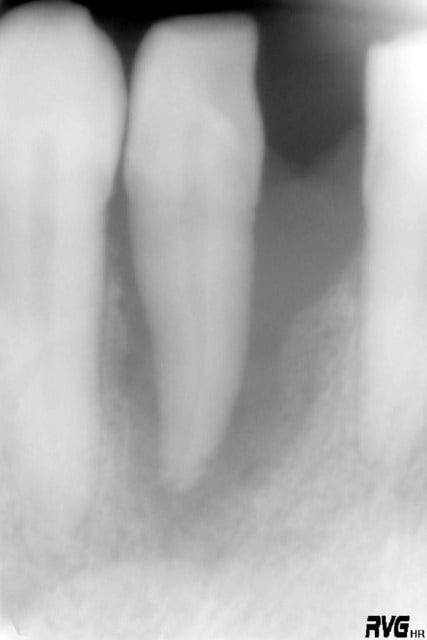

voici donc ce second cas ....

Oui ça ressemble à un canal latéral non obturé, d'autant que le TR parait étrangement rectiligne, même pour une incisive inf.

La cavité d'accès montre qu'une minéralisation rendait le traitement difficile.

Donc oui, un canal oublié.

c'est pas moi qui est fait l'endo ......d'ac avec toi steph ou ....une petite partie de la table vest a disparu ....par contre le parodonte s'est reformé au dessus